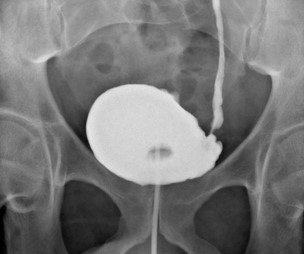

Follow-up at 3 months with MRI and flexible cystoscopy confirmed no evidence of recurrence (Figure 4). The patient maintained a satisfactory functional bladder capacity (300 ml) and reported an International Prostate Symptom Score (IPSS) of 5 with a storage score of 0.

Figure 4: Axial, sagittal and coronal views of T2-weighted MRI of the bladder showing normal bladder wall, with no evidence of local/ regional recurrence.